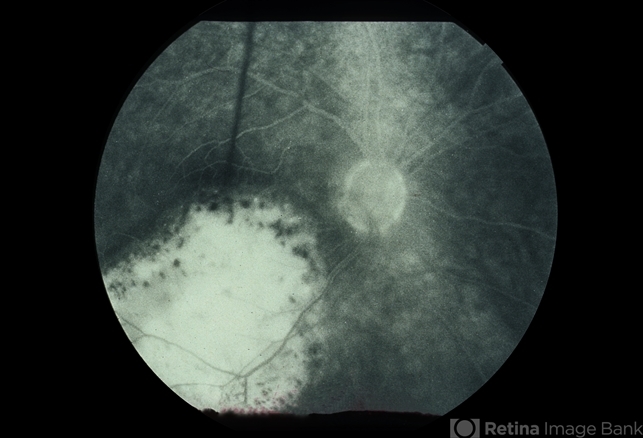

- Amelanotic Malignant Melanoma

- Condition/keywords

- malignant melanoma

- 75-year-old female, amelanotic malignant melanoma.